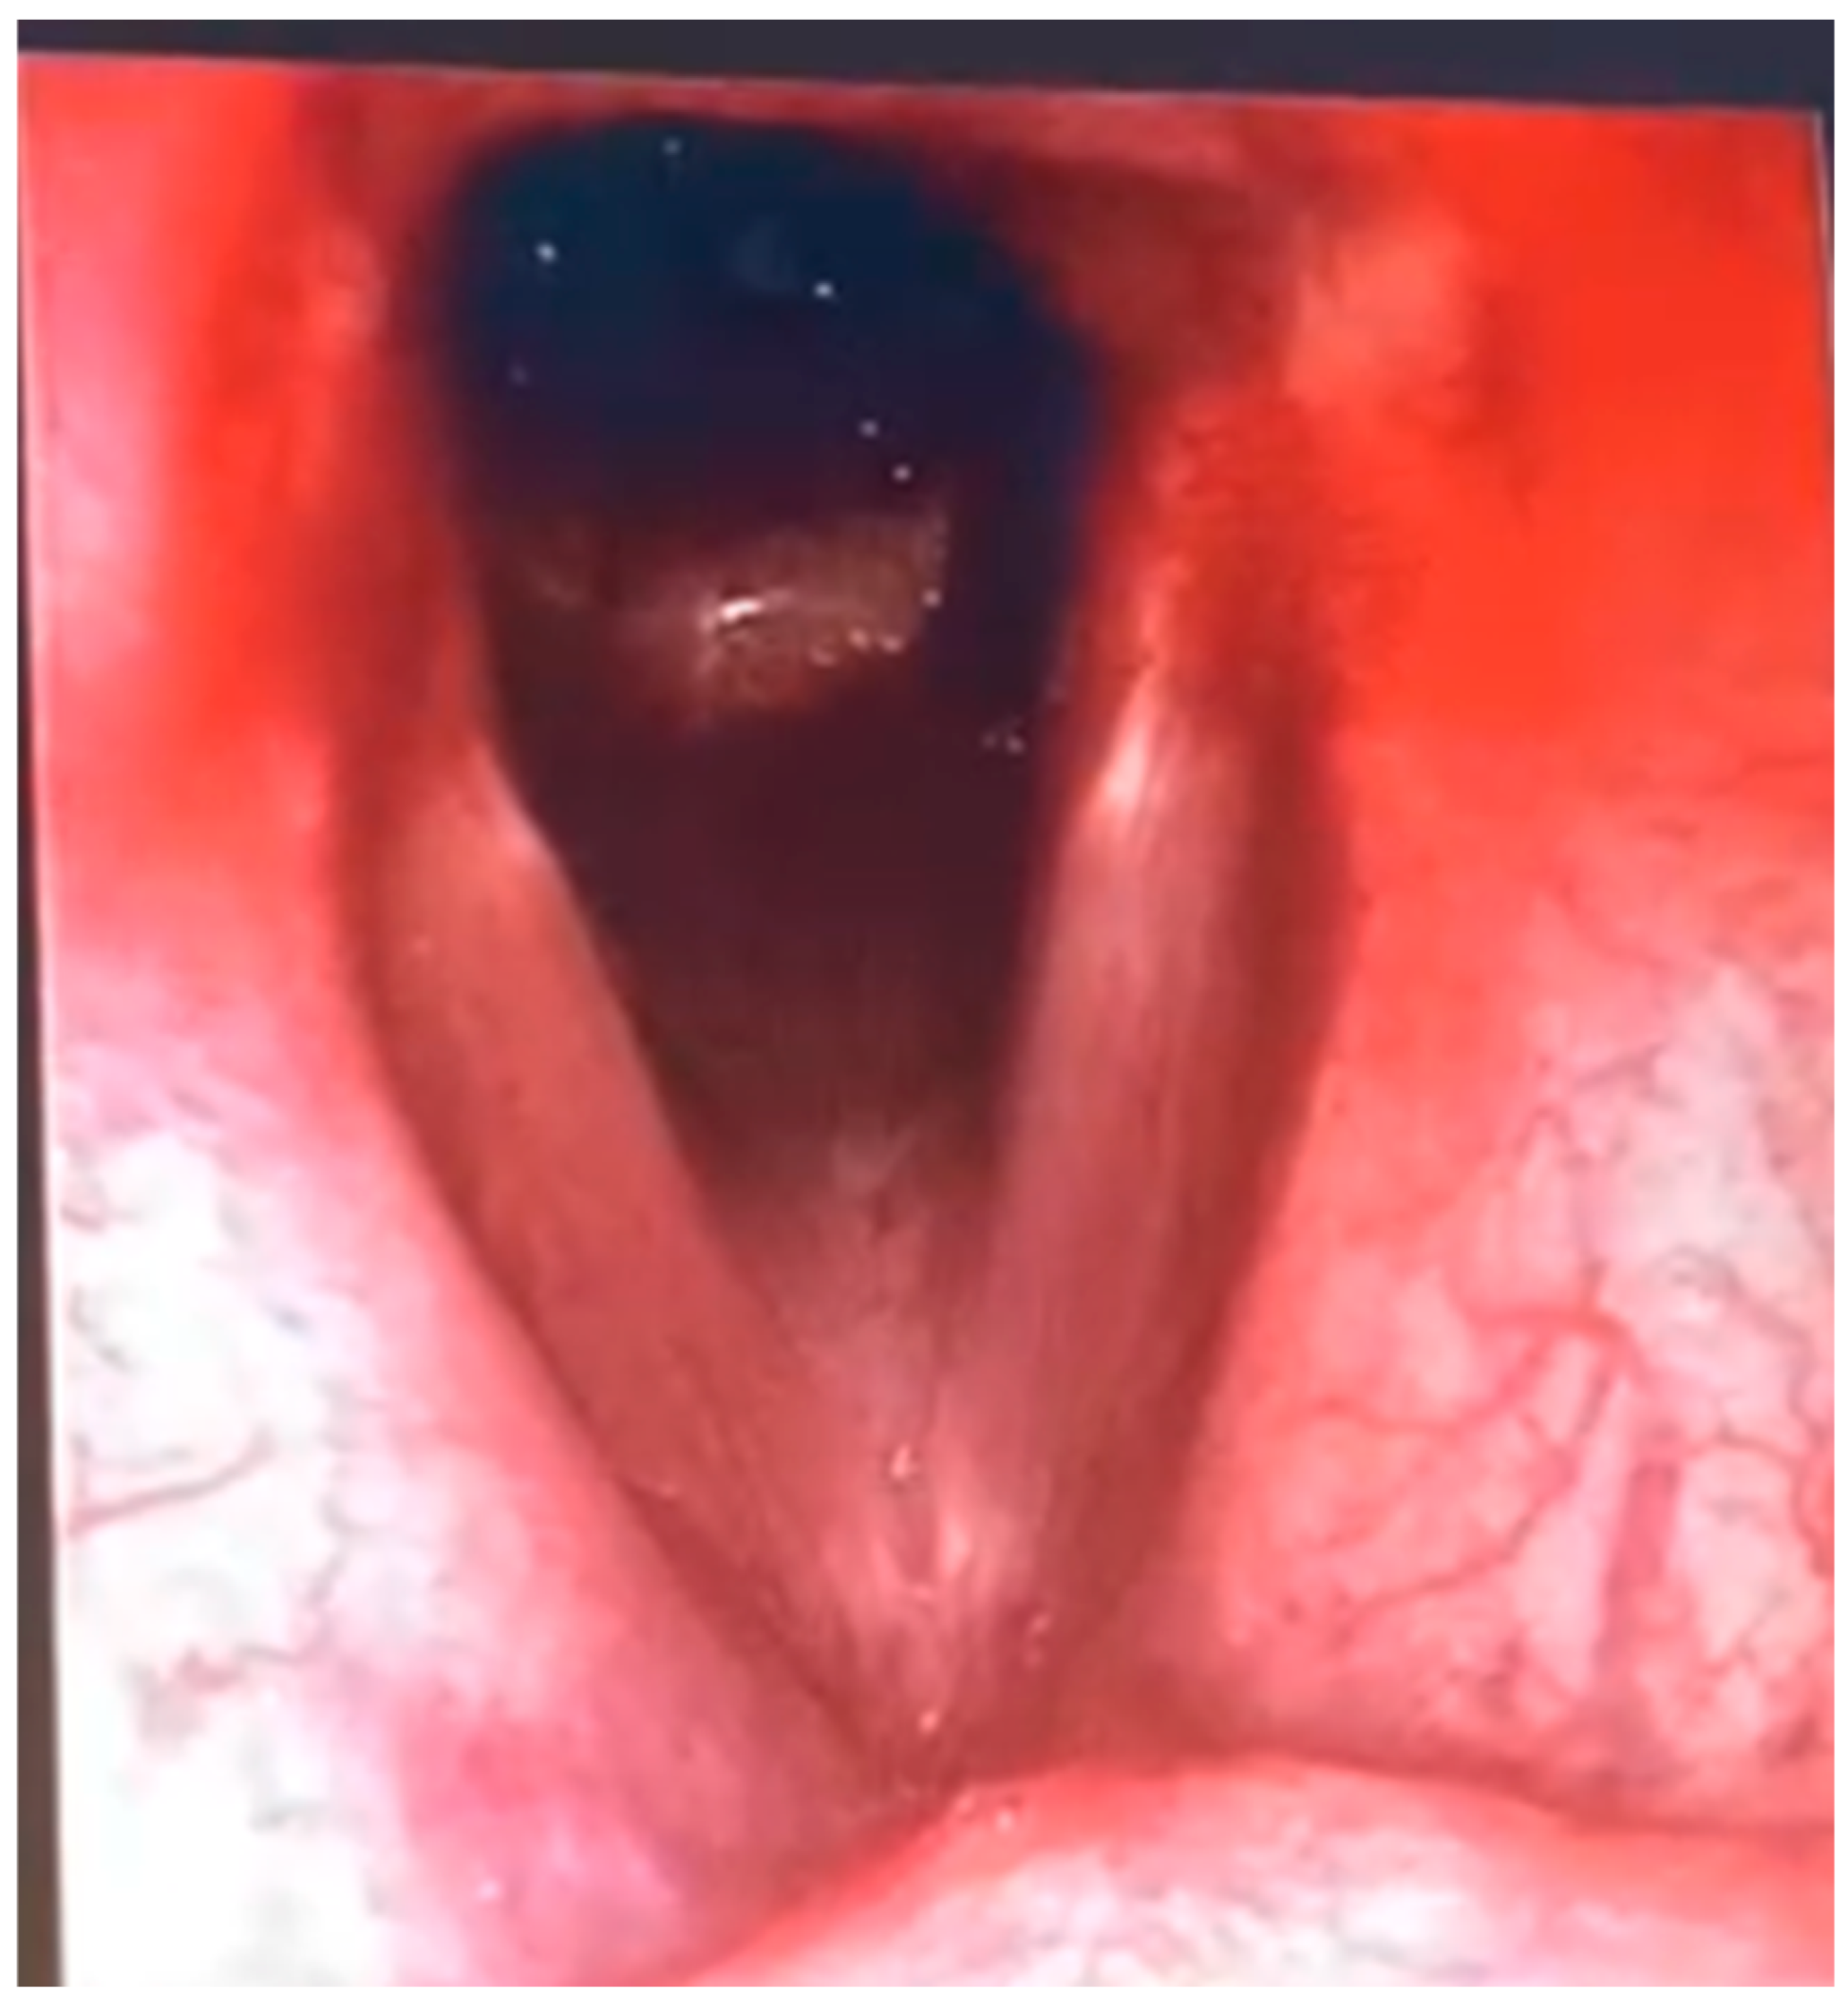

In the clinical case we observed, a 23-year-old male patient undergoing neurorehabilitation following severe traumatic brain injury (TBI) had been transferred to our facility with a pre-existing tracheostomy, previously performed due to episodes of food aspiration. Ten days after the tracheostomy, the patient exhibited a marked increase in oral secretions and clear signs of aspiration of the enteral feeding administered via NGT, with material leaking through the tracheostomy cannula. Frequent endobronchial suctioning became necessary. Chest auscultation revealed inspiratory crackles and reduced breath sounds at the lung bases. The patient had a tracheostomy with a reinforced no. 8 cannula in place, inserted due to a critical sub-cricoid tracheal stenosis, estimated at 90% (Figure 2).

Another crucial aspect in evaluating surgical eligibility is the precise timing of the procedure. Inappropriate timing—such as in the presence of clinical instability or active respiratory infections—could severely compromise the surgical outcome. Equally fundamental are the diagnostic–functional assessments requested by the thoracic team. For surgical planning, the thoracic team required a series of targeted investigations to define both the fistula’s anatomical features and the patient’s overall condition. These included a computed tomography (CT) scan of the neck and chest (Figure 2), a dynamic video of the patient in full cervical extension (Figure 4), videolaryngoscopy (Figure 3), as well as assessments of nutritional, neurological, and general medical status.

The CT scan (Figure 2) allowed clear visualization of tracheal narrowing below the cricoid and identified indirect signs of TEF, providing critical preoperative information (Figure 2). The dynamic video in maximal cervical extension is especially useful in patients with potential post-coma rigidity or dystonia, allowing the surgical team to pre-empt challenges in field exposure, especially with anterior tracheal approaches (Figure 4). Nutritional assessment included confirming the correct positioning of the PEG, which is essential to ensure appropriate nutritional support both before and after the operation. Lastly, neurological and general clinical evaluations were required to exclude haemodynamic instability, ongoing airway infections, or other contraindications to major thoracic surgery. Even partial neurological cooperation was considered a favourable factor.

Figure 2. CT reconstructions of the neck and chest in sagittal, coronal, and axial views in a patient with severe subglottic tracheal stenosis (90%) and suspected tracheoesophageal fistula (TEF). The armored tracheostomy cannula (size 8) is visible in situ. The images reveal a critical narrowing of the tracheal lumen and structural abnormalities consistent with a possible fistulous communication between the trachea and esophagus, warranting endoscopic evaluation and surgical indication.

The availability of diagnostic tools such as bronchoscopy, videofluoroscopy, and sagittal neck CT allows for fast and accurate assessment. Additionally, weaning from mechanical ventilation should be considered a fundamental prerequisite for selecting surgical candidates, as evidenced by better clinical outcomes in non-ventilated patients. As demonstrated in our patient (Figure 2 and Figure 3), the integration of sagittal CT imaging with endoscopic evaluation enhances early detection of subtle posterior tracheal wall defects that may be missed on axial-only views. This combined anatomical–functional approach has also been emphasized in recent reviews [6,10]. Our case further confirms that structuring a standardized evaluative pathway centered on interdisciplinary collaboration not only improves surgical outcomes but also enables a more timely and targeted rehabilitative approach. Although mechanical ventilation is not an absolute contraindication, partial or complete weaning remains a key factor in surgical eligibility, reducing the risk of perioperative complications and enhancing tissue healing.